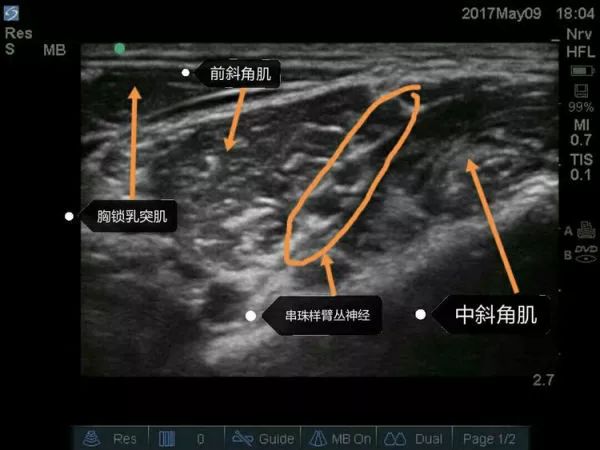

超声引导下臂丛神经阻滞要点

① 适应证:肩和上臂的手术。

② 探头的位置:横向放置在颈部,横跨颈外静脉表面,约锁骨上3-4cm。

③ 目标:局麻药在前、中斜角肌之间,臂丛的上、中干周围扩散。

④ 局麻药: 15-25ml。

超声下肌间沟水平臂丛的走行图像,上面是胸锁乳突肌,左右是前、中斜角肌。肌间沟水平下可清楚看到呈串珠样的臂丛,C5、C6、C7等。请大家注意下,有的时候能看见5个“串珠”,不要以为是臂丛的5个根即C5、C6、C7、C8、T1,肌间沟往往是在颈椎7水平,怎么可能看到C8、T1,其实就是C5、C6、C7,那为什么是5个“串珠”?因为C6及C7在肌间沟水平已经分出2根,要避免在这2根汇合处之间穿刺而造成C6及C7的神经损伤。